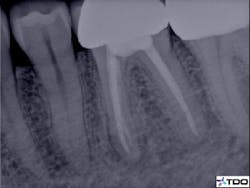

Figure 2 demonstrates a case with failing endodontic therapy. The mesial canals show inadequate obturation, and a periradicular radiolucent area is apparent. The tooth was retreated, and figure 3 shows the one-year follow-up. Note the resolution of the radiolucency. This case demonstrates the concept of removing the etiology of the bacteria with nonsurgical treatment.